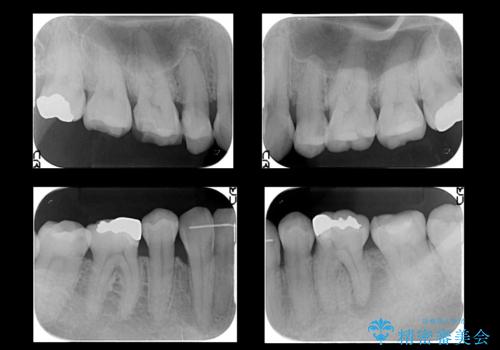

左下6番、左上4番は失活していたため、根管治療を行っています。

右上7・左上6:PGAインレー

右上8:PGAクラウン

左上4・左下6・右上56:ジルコニアクラウン

左上7・左下7:emaxインレー

での治療を行っています。

根管治療はDr.大元が行っています。